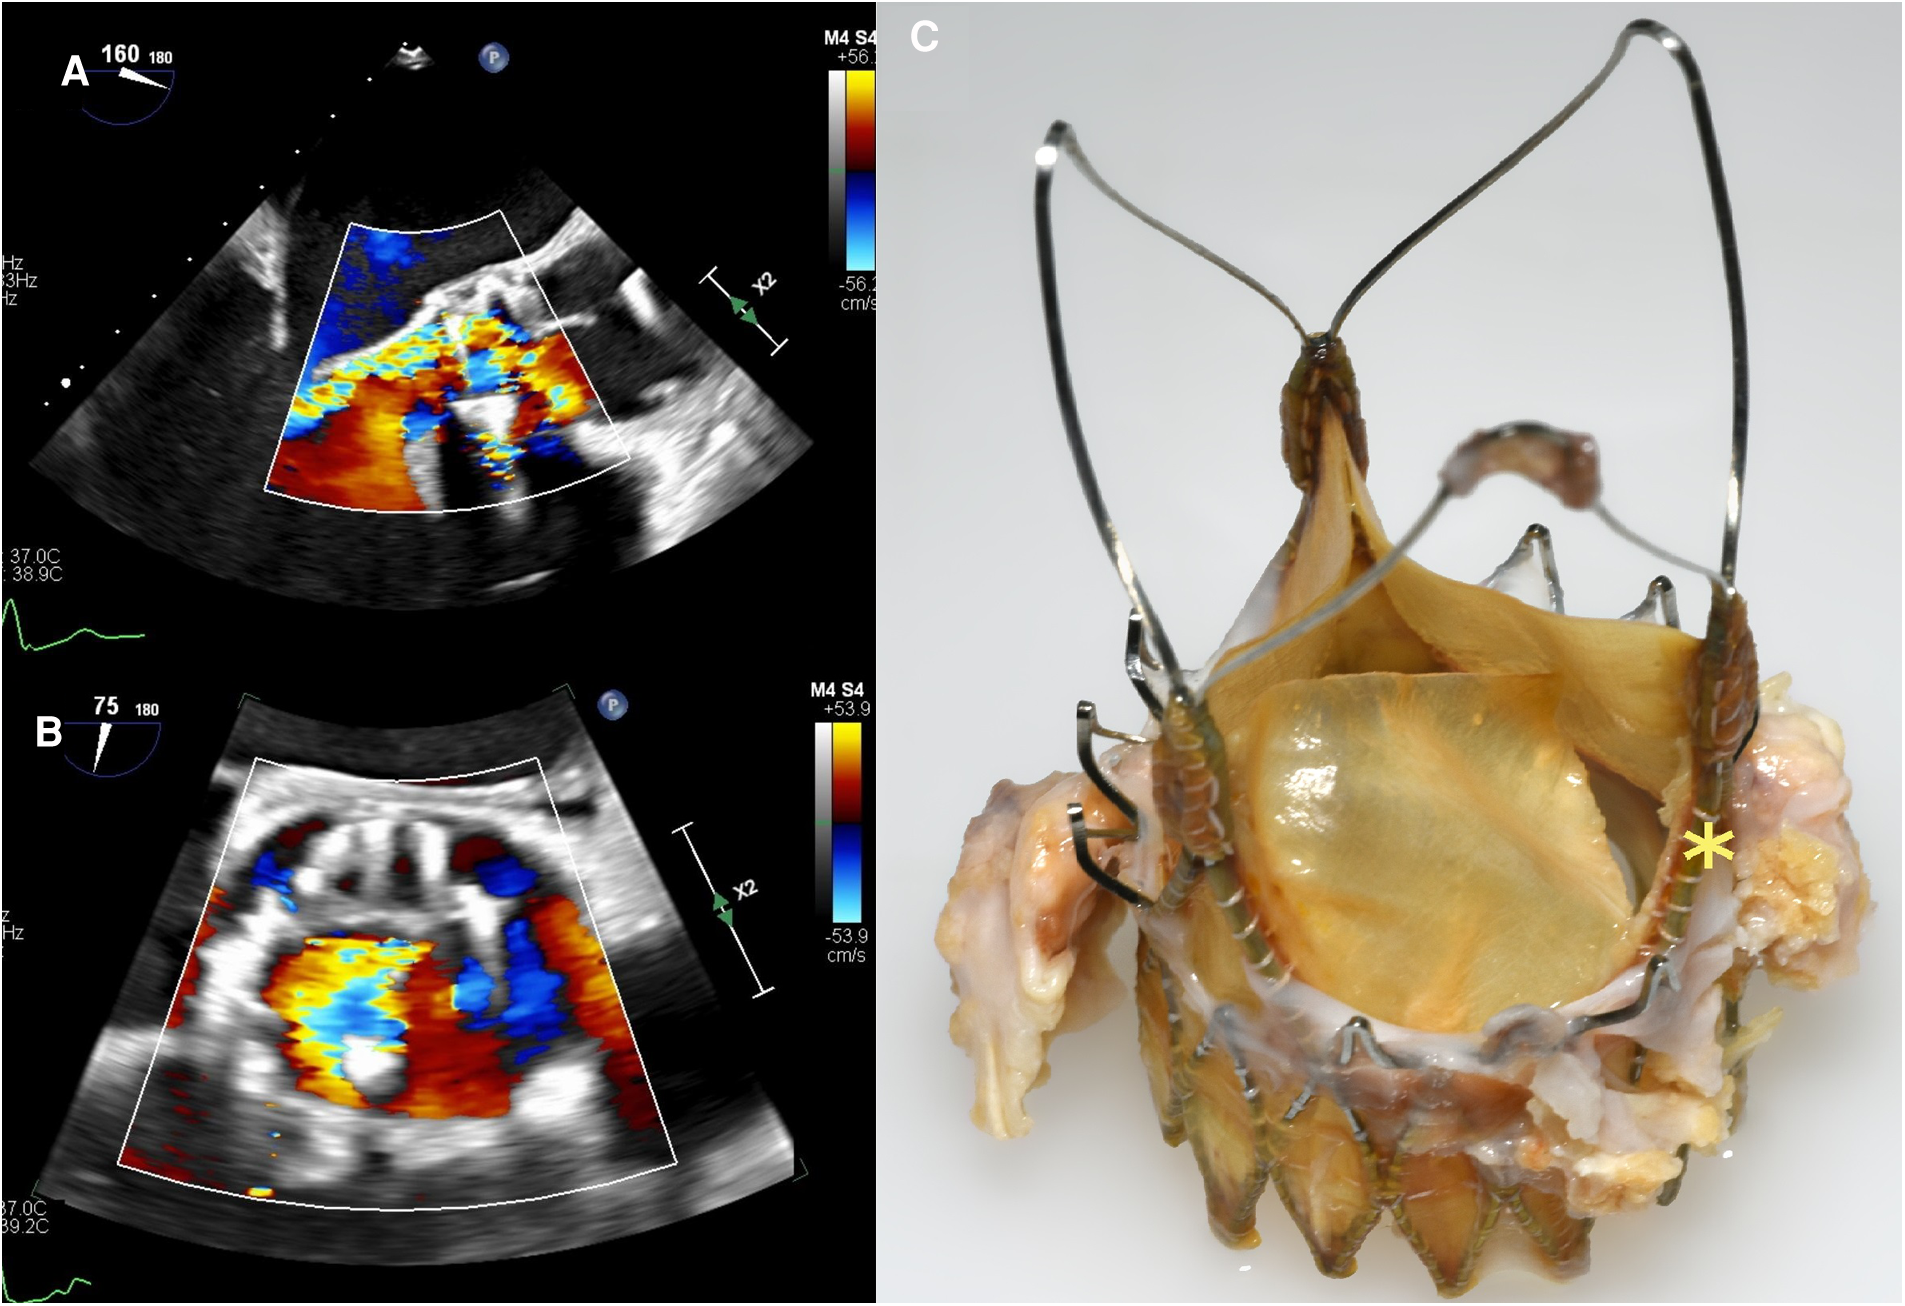

A 70-year-old man was implanted with ACURATE Neo (size M) for symptomatic, severe aortic valve stenosis. The procedure was unremarkable, and transthoracic echocardiography (TTE) at discharge showed a mean aortic transvalvular aortic gradient of 7 mmHg and trivial paravalvular regurgitation. Approximately 4 years (54 months) later, he presented to his regional hospital with rapidly progressive dyspnea. TTE revealed severe aortic valve regurgitation (AR). After transfer to our tertiary center, transesophageal echocardiography (TEE) demonstrated a well-seated TAVR prosthesis with severe intraprosthetic, eccentric AR (see Figures 1A,B). Transvalvular aortic gradients were slightly elevated (mean pressure gradient 18 mmHg). Blood cultures were negative. Considering the intermediate surgical risk of the patient, we opted for an emergent TAVR explant and surgical aortic valve replacement (SAVR). Intraoperative inspection of the prosthesis revealed a leaflet disruption with its adjacent strut in the noncoronary position (see Figure 1C). There were no signs of endocarditis. Extraction of the prosthesis was complicated due to extensive pannus arising from the heavily calcified native aortic valve. Due to subsequent lacerations of the aortic annulus, the aortomitral junction was reconstructed with a bovine pericardial patch, and a 23-mm stented bioprosthesis was implanted in the aortic position. The postoperative course was uneventful, and the patient was promptly discharged. After an internal review, the manufacturer was unable to identify the cause of prosthesis dysfunction. According to the manufacturer's archive, the referenced device had passed all tests during manufacturing and met all required specifications before approval for final distribution and sale.

Figure 1

Case 1: transesophageal echocardiography three-chamber view with color-flow Doppler (A) and aortic valve-centered short-axis view with color-flow Doppler (B) showing an eccentric, severe intraprosthetic regurgitation. (C) Explanted ACURATE Neo prosthesis with leaflet disruption with its adjacent strut in the noncoronary position (yellow asterisk).